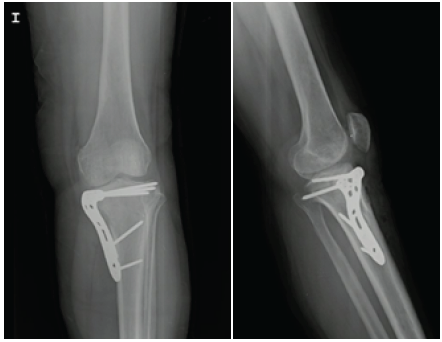

Conventional knee radiographs (Figure 1) showed a small round epiphyseal lytic lesion with well-limited borders at the medial tibial plateau, although no periosteal reaction or other associated changes suggesting local aggressiveness were observed.

Figure 1 Anteroposterior and lateral knee radiographs showing a lytic lesion at the medial level of the proximal epiphysis of the left tibia.

Figure 5 Postoperative x-ray showing recovery of the joint surface and proximal tibia anatomy.